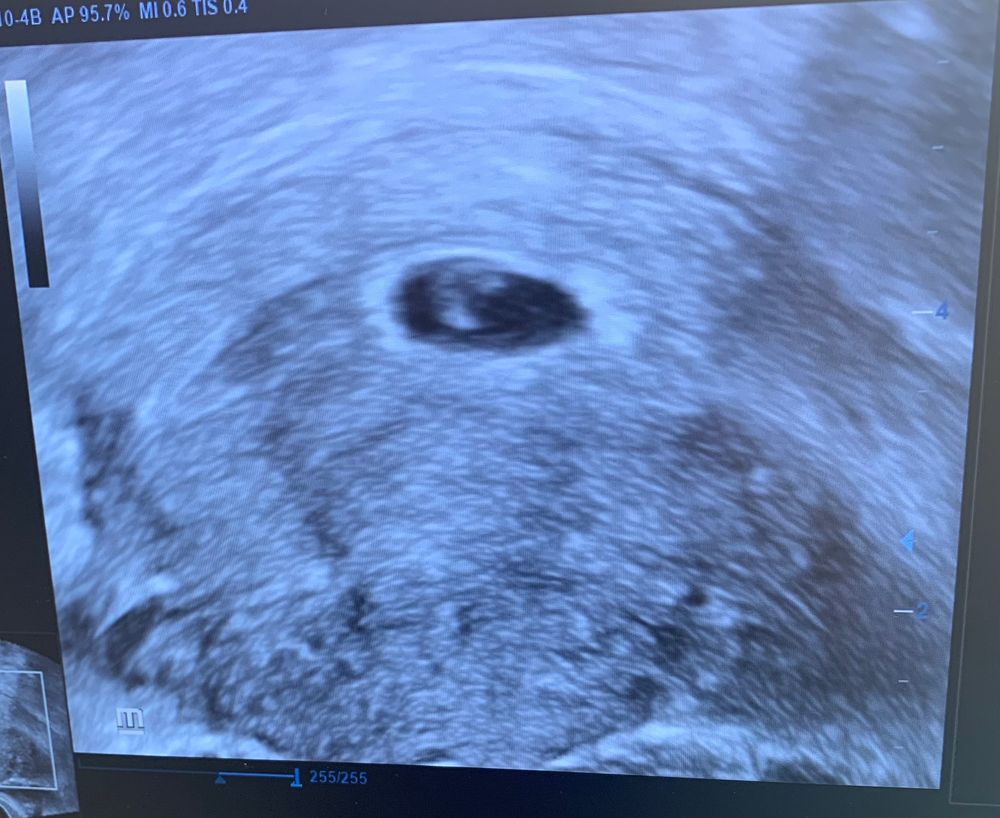

Эмбрион не виден

Насчёт переносили двоих я вам точно могу сказать,что это не значит что прижились оба.Во вторых даже если эмбрион и не визуализируется(в чем я сомневаюсь и очень поскольку смотрю сейчас на фото)это не повод нервничать,потерпите немножко,выйдет ваша врач и пусть она делает узи

У меня эмбриончика увидели в 5 нед 6 дн по месячным. на фото, возможно, жм а то что перенесли 2, а увидели одно пя, значит прижился 1

Ну не факт если переносили 2, то 2 и останутся. А какой у вас дпп? То что на узи на эмбрион не похоже

Я вижу одно плодное яйцо и видимо хорион💁‍♀️ Эмбрион не вижу 🙈 Какой дпп?